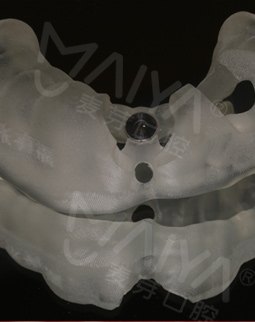

经过数字化的拍片检查后发现,我的牙周情况还是蛮不错的,可以用MAC数字化精确种植牙实现8分钟种稳一颗牙,而且工作人员说我可以作为直播案例主角分享自己的故事,感到非常荣幸。

在种牙之前,这里的硕博专家给我讲解了种植牙的相关知识,而且通过数字化的设备模拟出种牙的全过程,打消了我的种种疑虑。专家说,随着数字化在口腔领域的应有,种牙已经不像之前那样等待时间长、创口大、步骤多,而是实现即种即用,并且利用数字化导航设备种牙更精确,不用仅仅依靠医生经验去进行种牙,手术前一周我已经做了取模,今天准备种牙!